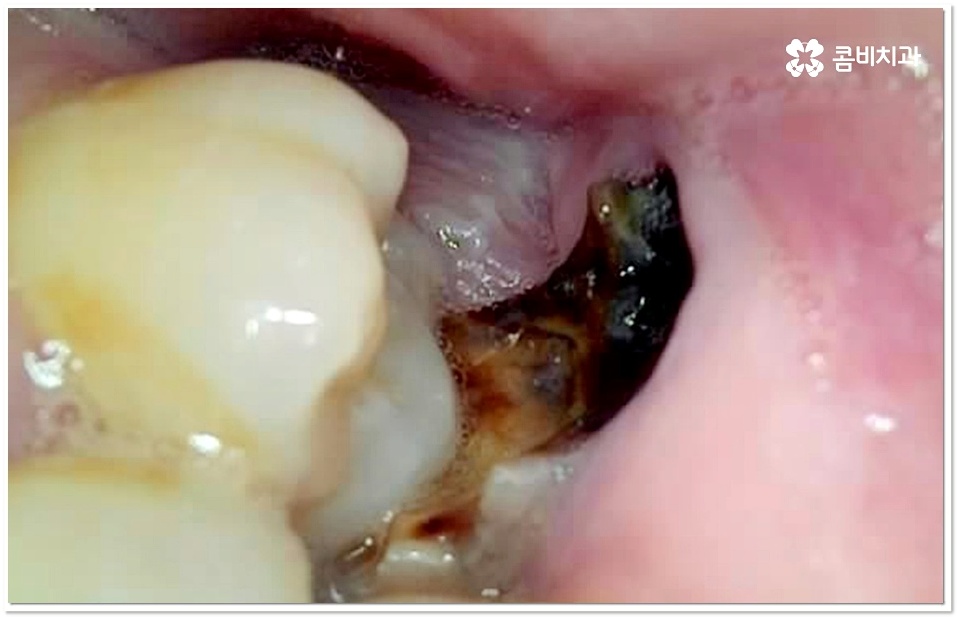

충치 초기라고 하더라도 만약 저작면이 아닌 인접면 충치가 생긴 경우에는 상황에 따라 레진 치료가 아닌 인레이 어금니 충치치료 방법을 쓸 수 있는데요. 이때 치아 옆면을 재건해야 하는 경우처럼 까다로운 케이스에 있어서는 더욱 세심한 주의력과 숙련된 노하우가 필요할 거예요.

특히 20살 전후로는 사랑니 때문에 인접면 충치가 자주 발생할 수 있으니 신경써 주시길 권유드리고 있는데요. 어금니 뒤쪽으로 사랑니가 나올 때 비정상적으로 맹출이 되어 비스듬한 각도로 어금니와의 사이에 좁은 틈새를 만들게 되면 음식물 찌꺼기가 잘 끼고 쉽게 빠지지 않아 더욱 충치나 잇몸 염증이 유발되기 쉬우니 신경써서 관리해 주시길 바라고 있어요.